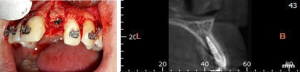

A Straumann bone level tapered (BLT) implant with a 3.3 mm diameter and 11 mm length, classified as a rock-solid type of dental implant, was then placed (Figure 7 and 8).

Figure 7 and 8: Final implant position and CBCT control image two years later